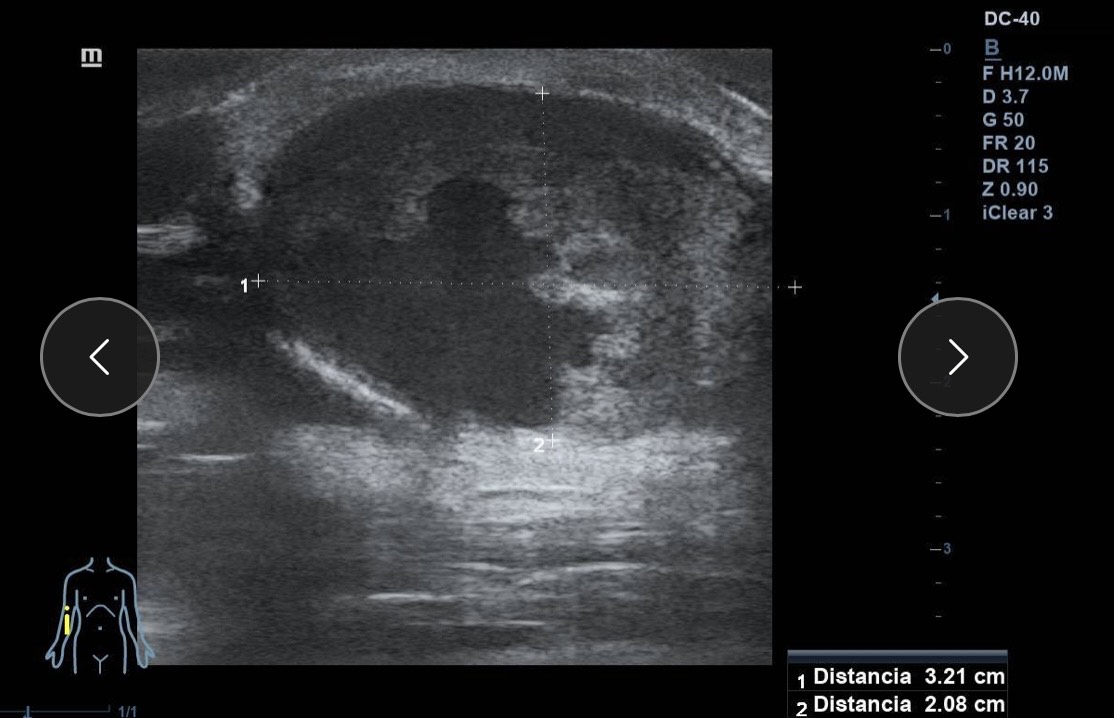

Ante la sospecha de patología vascular, se realiza ecografía clínica en la consulta.

Hallazgos ecográficos

Ecografía Doppler: dilatación aneurismática sacular de la arteria braquial (3 cm), bien delimitada, con trombo mural no oclusivo y flujo turbulento. Flujo arterial proximal y distal conservado. Sin signos de rotura ni hematoma adyacente.